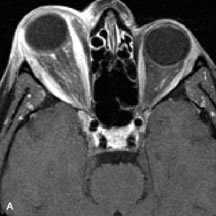

PATIENT PREPARATION Before MRI is performed, patients must be screened and prepared to avoid the potential hazards associated with the strong magnetic field. Patients who have ferrous aneurysm clips or cardiac pacemakers, who depend on life-support equipment, or who retain a possible metallic intraocular foreign body are not candidates for this imaging modality. MRI cannot be performed on obese patients who cannot fit into the bore of the magnet. Patients who are claustrophobic may not tolerate a prolonged period of study within the confines of the magnet, whereas others might do well if given a mild sedative. All worn metallic objects (e.g., necklaces, watches) should be taken off, credit cards set aside, and eye makeup removed before entering the room containing the magnet.5,20,34,35,36 NORMAL ORBITAL ANATOMY T1-weighted images provide the best anatomic details of the orbit because they display superior contrast resolution between normal structures (see Fig. 8). The vitreous has a long T1, resulting in an intermediate signal similar to brain, whereas the crystalline lens and sclera appear dark because of a longer T1 and short T2. The extraocular muscles, like all skeletal muscles, demonstrate a moderately long T1 and short T2 and highly contrast with the intense signal of the surrounding orbital fat (adipose tissue has an extremely short T1). The lacrimal glands appear as mottled areas of reduced intensity of the signal from the orbital fat in the lacrimal fossa. The optic nerves are seen with the same signal intensity as brain white matter and are hypointense relative to the orbital fat because their Tl is longer than the Tl of fat but shorter than the Tl of water. Cortical bone is not well delineated because it contains little free water, yielding minimal signal in MRI, and thus appears dark on all pulse sequences. This feature explains why MR images of the orbital apex and intracanalicular portion of the optic nerves are superior to comparable CT scans. Partial volume averaging of the bones in these regions obscures soft tissue details on CT images, whereas MRI reveals the signals only from the soft tissue structures with no cortical bone input. Bone marrow, on the other hand, is seen as a relatively intense signal because of its high fat content (see Fig. 8).37,38 T2-weighted pulse sequences are not ideal for imaging normal anatomy; however, they are particularly useful in revealing pathologic conditions (see Fig. 9). T2-weighted studies are most easily recognized by a bright vitreous signal. ORBITAL DISEASES Vascular Lesions Cavernous hemangiomas appear as well-circumscribed, smooth, usually intraconal masses that are isointense to muscle on T1-weighted images and hyperintense on T2-weighted images (Fig. 12). Patchy early enhancement is typically followed by diffuse, more homogeneous enhancement.39 The internal architecture of the mass, including septation and internal vasculature, may often be appreciated with high-quality orbital imaging.40 Lymphangiomas consist of ectatic vascular channels within a connective tissue stoma with varying degrees of lymphoid cellularity. On MRI, these tumors are typically poorly circumscribed, multicompartmental, and heterogeneous, often showing cystic dilations with fluid levels (Fig. 13). The signal characteristics within lymphangiomas vary considerably, reflecting cystic and solid components and the varying paramagnetic characteristics of blood at different stages of degradation.40–42 Acute hemorrhage appears hypointense on both T1- and T2-weighted formats. Methemoglobin present in subacute hemorrhage (3 to 14 days) leads to hyperintense signal on both T1- and T2-weighted images.41 A small percentage of lymphangiomas appear radiologically indistinct from orbital cavernous hemangiomas.43 Orbital varices are venous malformations that expand with increased systemic venous pressure, such as with Valsalva maneuvers. Because rapid acquisition of images during a Valsalva maneuver is important in imaging such a lesion, conventional or spiral CT is currently the modality of choice.44 MRI is an excellent modality for demonstrating enlargement of the cavernous sinus and dilation of the superior ophthalmic vein in patients with high-flow carotid-cavernous fistulas (Fig. 14).37MRA may be helpful in the evaluation of the venous outflow pattern. The rapidly flowing blood in these vascular structures carries the excited protons out of the section before they can be imaged, resulting in their dark appearance.5 In low-flow dural arteriovenous malformations, MRA may help define the arterial feeding vessels.45 Neural Lesions MRI is more effective than CT in delineating the intracranial optic nerves, chiasm, and optic tracts and, for this reason, is the preferred imaging modality in the evaluation of optic nerve disorders. The spatial relationships and image contrast of the orbital tissues with intraorbital optic nerve tumors is comparable between the two imaging modalities. The normal nerve is isointense to brain and appears enlarged and kinked owing to infiltration of an optic nerve glioma on T1-weighted images. Gliomas appear hyperintense on T2-weighted images and may be heterogeneous owing to cystic areas within the tumor. Contrast enhancement is variable.46 Intraorbital and intracranial optic nerve sheath meningiomas are usually isointense to cortical gray matter on Tl-weighted images and remain isointense on proton density studies (Fig. 15). Gd-DTPA is useful in delineating the intracranial extension of optic nerve meningiomas.7,47 The hyperostosis of bone and calcification associated with meningiomas are not demonstrated as well on MRI studies as on CT scans.20,37 Gd-DTPA–enhanced MRI also appears promising in the study of the permeability of the blood–brain barrier in selected optic neuropathies.22,48 MRI may reveal an enlarged optic nerve and some degree of contrast enhancement in cases of optic neuritis.49 Muscle Disorders Extraocular muscle enlargement in patients with thyroid-associated orbitopathy is demonstrated equally well with CT and MRI studies. However, the superior tissue contrast on MR images reveals better details of the relationships of the optic nerve to the thickened muscles at the orbital apex (Fig. 16).50 In addition, MRI may be able to differentiate between muscles that are enlarged as a result of edema and active inflammation and those enlarged because of fibrosis by their T2 relaxation times.21 Quantitative MRI was not found to be accurate in predicting the success of low-dose orbital irradiation.51 However, a muscular index relating the diameters of the rectus muscles to the bony orbital dimensions was useful in predicting optic nerve compression.52 MRI is also effective in imaging orbital tumors of mesenchymal origin, such as rhabdomyosarcoma, particularly in the assessment of extension into the anterior and middle cranial fossae (Fig. 17).37 The lack of any pathognomonic radiologic features necessitates rapid orbital biopsy when rhabdomyosarcoma is suspected. Osseous Lesions In general, CT is the imaging modality of choice when details of quantity and quality of bone are needed; however, abnormalities of bones can be detected indirectly by MRI. Cortical bone appears black (signal void) on MR images because of its low proton density and free-water content. The absence or discontinuity of the signal void of the orbital walls may represent bony destruction or fracture. Hyperostosis associated with prostate metastases or meningioma is visualized as areas of black smudging.50,53 Diseases in which the bone is replaced by pathologic tissues with a high free-water content, such as fibrous dysplasia, are well demonstrated on MRI. An intermediate signal intensity on T1-weighted images and hypointense signal on T2-weighted images is representative of fibrous dysplasia. Enhancement on post–Gd-DTPA MR scans is seen and is more evident in areas that are less mineralized.54 Cystic Lesions Dermoid cysts appear as rounded, well-defined lesions typically contiguous with an orbital bony suture. The high-intensity signal on T1-weighted images is attributed to the sebaceous-produced lipid contents (Fig. 18).31,50 Mucoceles may demonstrate a hypointense or hyperintense signal on MR images, depending on the concentration of proteinaceous or inflammatory fluid components. The integrity of the bony walls of the expanded sinus cavities cannot be assessed on MR as well as by CT.37,50,55,56 A high-signal intensity on Tl- and T2-weighted images is characteristic of orbital chronic hematic cysts because of the blood-breakdown products within the cysts.57 Trauma Although soft tissue relationships are usually better demonstrated on MRI, the evaluation of craniofacial bony trauma is preferable with CT. For example, prolapse of orbital fat through a fracture site and hemorrhage of adjacent tissues are demonstrated in an MR image, but the actual fractured bone is not imaged. Three-dimensional MRI of the orbit in subacute trauma has been described,58 although its precise role is not currently established. MRI has been suggested to be superior to CT in detecting intraorbital wooden foreign bodies.59,60 In a series of penetrating orbital injuries with organic foreign bodies, however, MRI was able to identify the foreign body in only four of seven cases.61 With an in vitro model for wood foreign body, McGuckin and colleagues concluded that CT was the imaging modality of choice.62 A careful history and, in selected cases, plain films to rule out a metallic foreign body are crucial before MRI is considered in patients with periocular trauma. MRI is particularly helpful in the detection and characterization of subperiosteal hematomas of the orbit (Fig. 19). They are most commonly seen in the subperiosteal space of the superior orbit as well-defined masses following a traumatic injury. The signal intensity varies depending on the acute, subacute, or chronic nature of the hematoma, based on the stage of blood degradation. Fresh hemorrhages are hypointense on T1-weighted images and hyperintense on T2 images. Hematomas that are 1 to 7 days old are hypointense on both T1- and T2-weighted images. T1-weighted images of hematomas more than a week old are hyperintense due to the oxidation of deoxyhemoglobin to methemoglobin, whereas the T2 images remain hypointense.63 Metastatic Tumors Breast carcinoma metastatic to the orbit has been demonstrated to be hypointense to the surrounding orbital fat on T1-weighted studies and hyperintense on T2-weighted images and has an affinity to the extraocular muscles (Fig. 20).50,64 The MRI characteristics of prostate carcinoma metastatic to the orbit have been described as involving the greater and lesser wing of the sphenoid, orbital roof, and optic canal. Diffuse bone hypertrophy with isointense or slightly hyperintense tissue on T1-weighted images represents the osteoblastic carcinomatous bone infiltration. Contrast enhancement is variable on T1-weighted and fat-suppressed images.65 Most other metastatic tumors also have a lower intensity signal on T1-weighted images and appear to displace or infiltrate normal orbital structures; however, their signal characteristics are variable on T2-weighted MR images.66 Many metastatic tumors demonstrate bright contrast enhancement with Gd-DTPA. Infectious Disorders MRI findings of preseptal and orbital cellulitis typically include increased signal intensities on T2-weighted images of the eyelids and orbital fat, respectively, due to the increased water content of the tissues. Since most cases of bacterial orbital cellulitis are associated with paranasal sinusitis, hyperintense signals of the affected sinuses may also be found on T2-weighted images as well as enhancement of polyps and granulation tissue on postgadolinium T1-weighted MR images. Subperiosteal abscess formation may occur due to contiguous spread of infection from the paranasal sinuses and appear on MRI as an area of intermediate signal on T1-weighted and proton-weighted MR images. The abscess may appear slightly hyperintense compared with muscle on T2-weighted scans with the necrotic contents having the greatest intensity.67 MRI and MRV are more sensitive than CT in revealing cavernous sinus thrombosis. Engorgement of the cavernous sinus, extraocular muscles, and ophthalmic veins is seen with hyperintensity of the thrombosed sinuses evident on all pulse sequences. The enlarged, thrombosed superior ophthalmic vein appears less hypointense than the normal contralateral ophthalmic vein, and hyperintensity within the lumen of the vessel may be seen on T1- and T2-weighted MR images.68 Inflammatory and Lymphoproliferative Lesions Inflammatory conditions of the orbit, both idiopathic (inflammatory pseudotumor) and those of known causes, have been found to be hypointense to fat and isointense to muscle on Tl-weighted studies and isointense or slightly hyperintense to fat on T2-weighted images (Fig. 21).50,64,69 The more fibrous or sclerosing varieties have less signal intensity on T2-weighted images. Marked enhancement is seen in pseudotumor infiltrates after gadolinium administration.70 The same signal characteristics are demonstrated in patients with Tolosa-Hunt syndrome, with mass lesions seen in the cavernous sinuses and orbital apices.71 Lymphomas have MRI characteristics similar to those of inflammatory lesions in that they are hypointense to fat and isointense to muscle on T1-weighted images (Fig. 22). They may appear hyperintense to fat on T2-weighted images, perhaps owing to less fibrosis than that seen in orbital inflammatory pseudotumor, although this is not a consistent finding.31,50,66 Lymphoid tumors typically enhance moderately after contrast injection. Unfortunately, studies have shown that tumor density and homogeneity are similar between inflammatory and malignant orbital infiltrates, and MRI cannot differentiate these lesions.72,73 Lacrimal Gland Tumors Lacrimal gland lesions present special problems in diagnosis and management. Pleomorphic adenoma (benign mixed tumor) should not be biopsied, but rather excised in toto. On the other hand, for lymphoma and inflammatory infiltrates, incisional biopsy is more appropriate than complete excision of the lacrimal gland. Thus, preoperative clinical and radiologic evaluation are especially crucial in planning appropriate surgical management. Pleomorphic adenomas demonstrate long T1 and T2 signal characteristics. They may show heterogeneity on T2-weighted images74 and moderate to marked enhancement with contrast.75 Signal characteristics of adenoid cystic carcinoma include hypointensity to fat on T1-weighted images, hyperintensity to fat with increased T2 weighting, and isointensity to fat on proton density-weighted studies (Fig. 23).31,75 Secondary bony alterations of the lacrimal fossa associated with lacrimal gland tumors, such as remodeling (benign mixed tumor) or destruction (adenoid cystic carcinoma), are seen indirectly on MR images; however, bone windows on CT scans provide better delineation of these changes. In contrast to the round or globular appearance of benign or malignant epithelial tumors of the lacrimal gland, lymphoproliferative tumors usually appear to be molding or draping onto the globe and the surrounding bony orbit. LACRIMAL DRAINAGE SYSTEM DISORDERS MRI with surface coils provides excellent spatial resolution and tissue-specific signal intensities of the lacrimal drainage system. These parameters have been found useful to more accurately demonstrate the extent of lesions in the lacrimal sac and differentiate long-standing mucoceles from solid tumors than CT.76 Physiologic studies in patients with tearing disorders now include MR dacryocystography, in which Gd-DTPA is either placed topically in the conjunctival fornix or injected by cannulation into the lacrimal sac. They provide a detailed morphologic and functional analysis of the lacrimal excretory system; however, they are no more sensitive than digital-subtraction dacryocystography or CT dacryocystography.77–79 INTRAOCULAR TUMORS On MRI, uveal melanomas have a typical appearance that helps to differentiate them from other primary and secondary intraocular tumors as well as choroidal detachments. Pigmented melanomas are hyperintense on Tl-weighted images, hypointense on T2-weighted studies, and hyperintense on proton density–weighted examinations (Fig. 24).30,31,50,80–82 These signal characteristics have been attributed to the paramagnetic properties of melanin because of stable free radicals that shorten the T1 and T2 relaxation times. Moderate enhancement is seen on postgadolinium T2-weighted images. Gadolinium-enhanced T1-weighted images are particularly sensitive in detecting choroidal melanomas.83 MRI may be less sensitive in detecting extrascleral extension of tumor than echography performed by an experienced ultrasonographer.84 Tumors metastatic to the choroid are hyperintense on T1- and T2-weighted images.24 The signal characteristics, however, may be similar to those seen with choroidal melanoma. Choroidal hemangiomas, on the other hand, have an intermediate signal on T1-weighted sequences and become hyperintense on T2-weighted images50 as well as proton density–weighted images.81 Retinoblastomas display moderate signal intensity on T1-weighted studies and a low signal on T2-weighted images.31,80,85 Calcification can be easily detected by CT and ocular ultrasonography but is not imaged by MRI.25,50 The presence of optic nerve involvement is best evaluated by MRI. ACQUIRED ANOPHTHALMIA When an eye is removed owing to tumor or trauma, an implant is typically placed in the intraconal space. MRI may be useful in defining the size, shape, and position of such orbital implants.86 Porous hydroxyapatite or polyethylene implants are preferred by many surgeons performing enucleation or evisceration. A porous implant offers the possibility of supporting a motility coupling peg to increase the movement of the overlying prosthesis. MRI with contrast is used by some surgeons to evaluate the degree of fibrovascular ingrowth in hydroxyapatite87 and porous polyethylene88 implants prior to motility peg placement. |